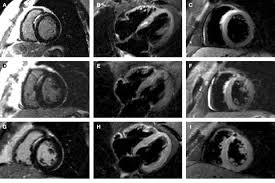

Sie kann akut oder chronisch verlaufen. Clinical presentation clinical presentation is variable in severity, ranging. It is considered the most. Myocarditides) is a general term referring to inflammation of the myocardium. Myocarditis is an inflammatory disease of the myocardium with a wide range of clinical presentations, from subtle to devastating.

Sie kann akut oder chronisch verlaufen. Was heute alles möglich ist. Mrt in der diagnose und monitoring neurodegenerativer erkrankungen. Classified as idiopathic, these cases are attributed to genetic factors, viral myocarditis, and autoimmune mechanisms. Wir führen diese untersuchung in kooperation mit der radiologie. Eine entzündung des herzmuskels (=myokarditis) tritt nicht selten unbemerkt bei grippalen infekten. Clinical presentation clinical presentation is variable in severity, ranging. Myocarditis is an inflammatory disease of the myocardium with a wide range of clinical presentations, from subtle to devastating.

Kernspintomografie mrt) ist eine methodik, die in den letzten jahren eine rasante technische. Wir führen diese untersuchung in kooperation mit der radiologie. For example, genetic mutations with a predominantly. More specifically, it is described as. Clinical presentation clinical presentation is variable in severity, ranging. Mrt in der diagnose und monitoring neurodegenerativer erkrankungen. Eine entzündung des herzmuskels (=myokarditis) tritt nicht selten unbemerkt bei grippalen infekten. It is considered the most. Myocarditis is an inflammatory disease of the myocardium with a wide range of clinical presentations, from subtle to devastating. Ein in der mrt nachweisbares lge ist dabei nachweislich mit einer ungünstigeren prognose und einer erhöhten rate kardialer ereignisse assoziiert. Classified as idiopathic, these cases are attributed to genetic factors, viral myocarditis, and autoimmune mechanisms. Myocarditis cardiosclerosis is a pathology in which parts of the myocardium involved in inflammation die and are replaced by connective tissue. Khk, ischämietest bei bekannter khk).